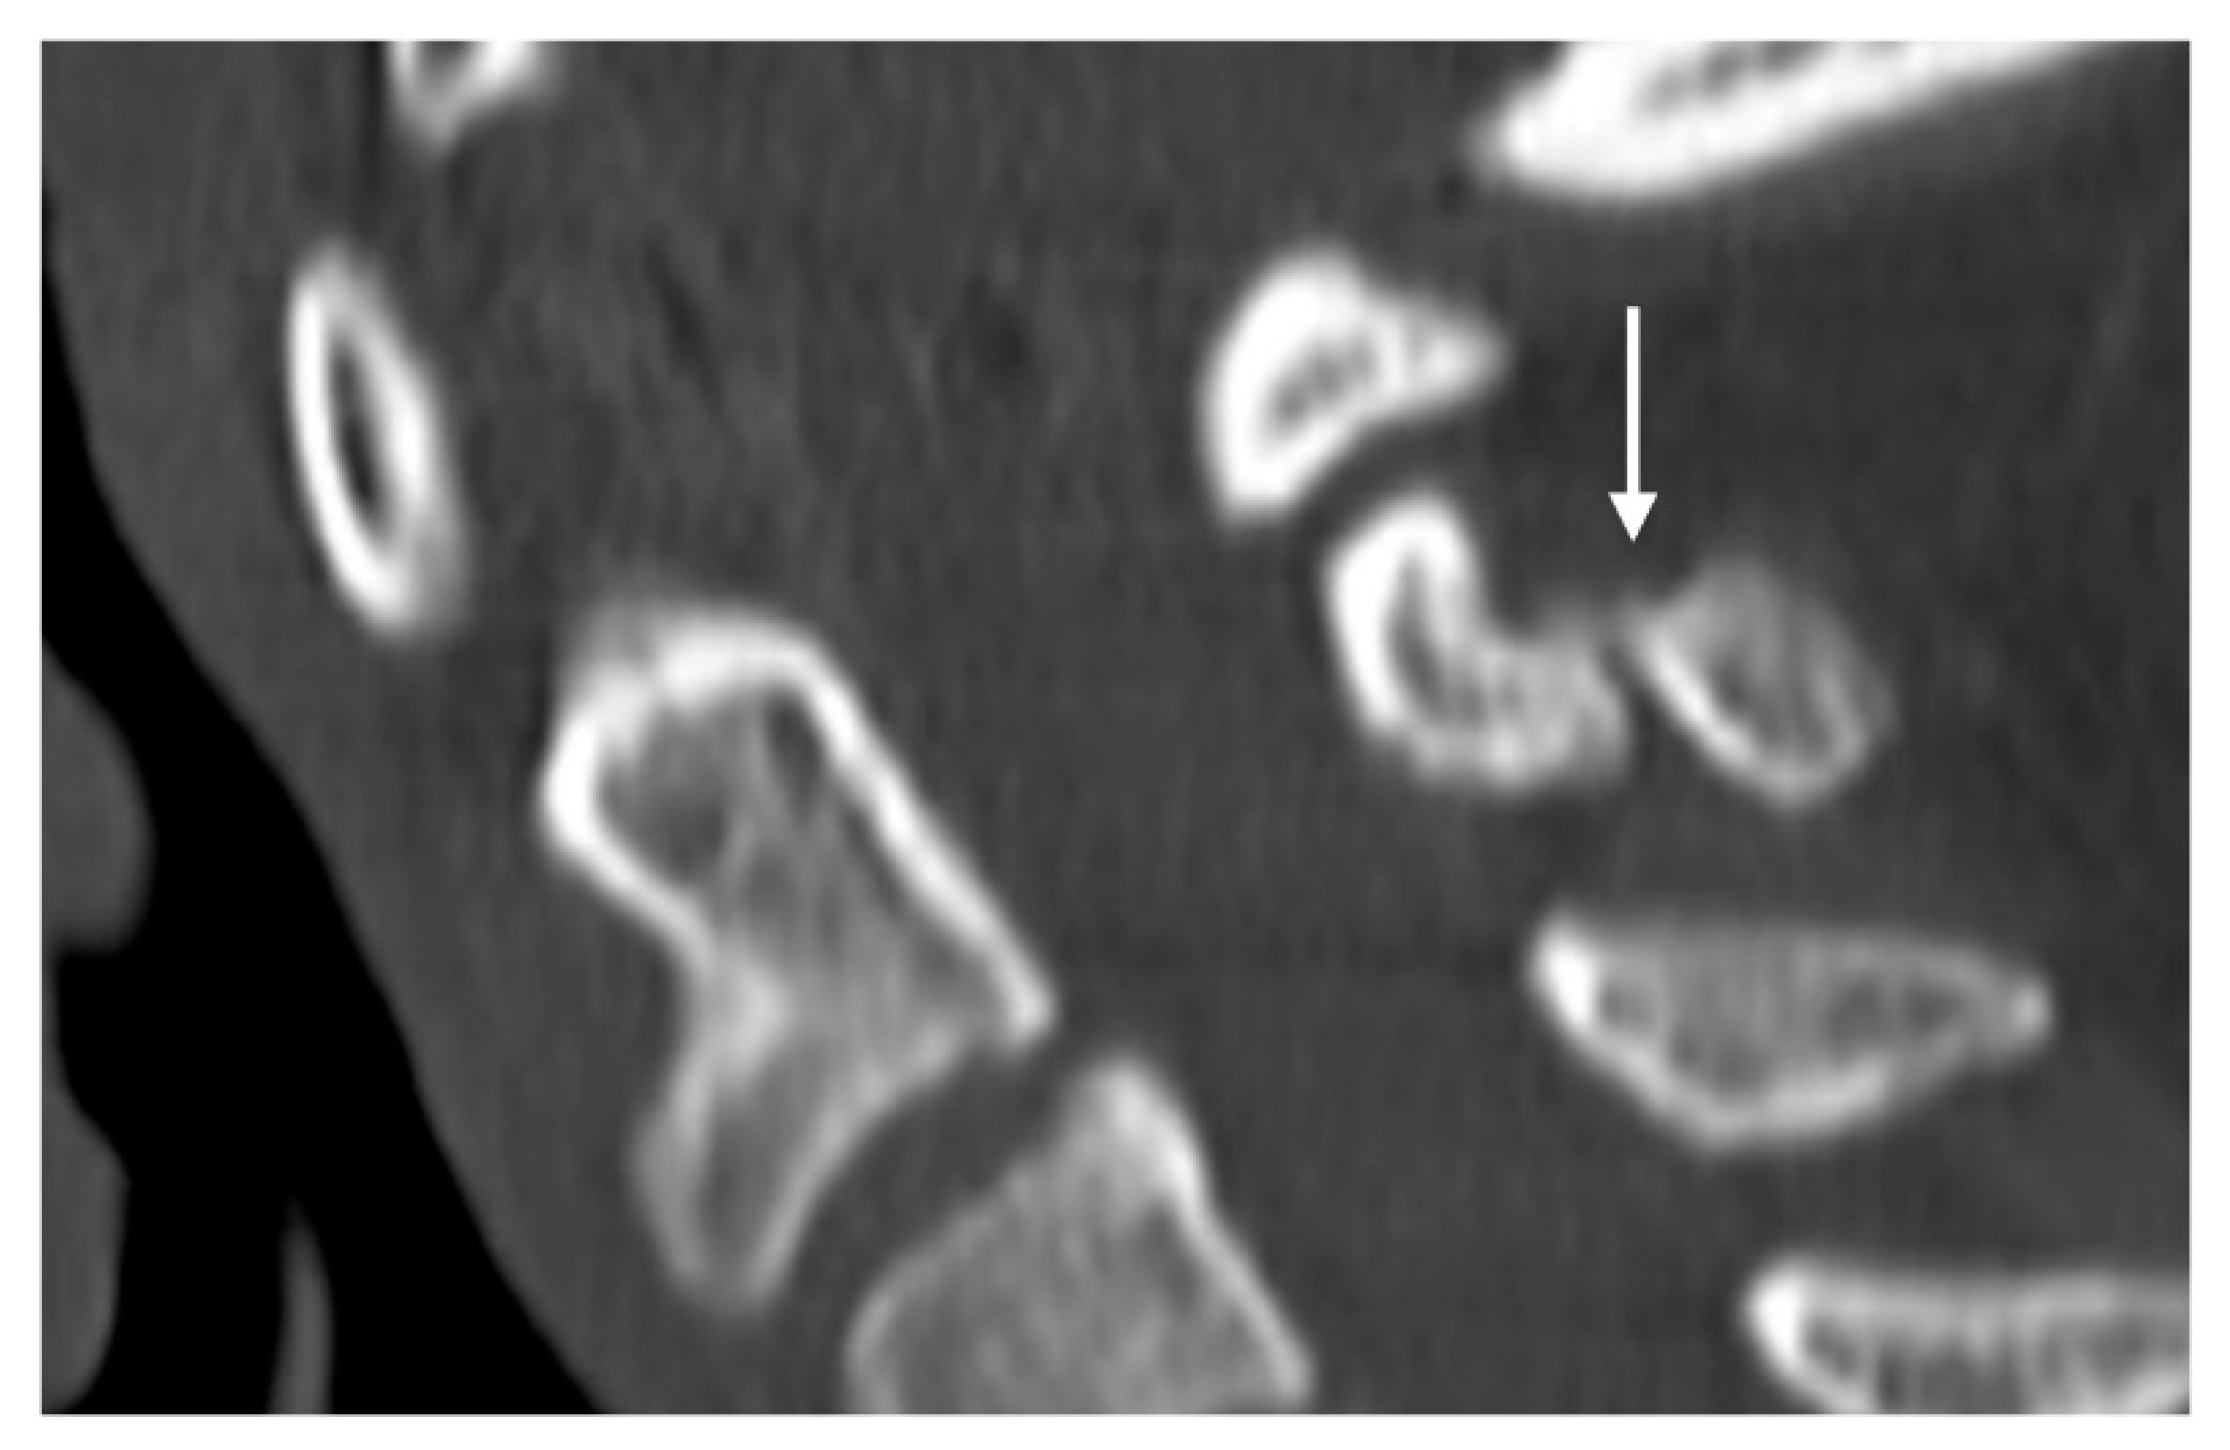

These fractures can be readily visualised on a plain film or CT, where a displaced fragment without a sclerotic edge can be seen. MR demonstrates bone marrow oedema (T2 hyperintensity) at the fracture site with frequent oedema within the interspinous ligament. Chronic non-union is a complication and is characterised by sclerosis and/or irregularity of the fracture line (Figure 8) and by resolution of oedema on MRI.

Figure 8.

Sagittal CT image demonstrating a non-united fracture of C2 spinous process (white arrow).